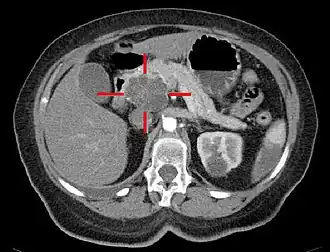

| TAC com coloração artificial e elevado nível de contraste. A cruz delimita um adenocarcinoma macrocístico na cabeça do pâncreas. | |